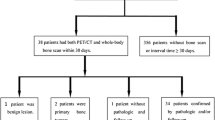

Out of a series of 44 children and adolescents referred for whole-body MR imaging only in 16 patients with histologically proven malignant lesions (nine boys and seven girls; age 4 months to 24 years; median 9 years 7 months), a whole-body MRI using a STIR sequence and a 99mTc-methylene diphosphonate planar scintigraphy were performed with a time interval of 5 weeks maximum between scintigraphy and MRI. In the remaining 28 patients, the time interval between the both modalities was over 5 weeks or only one of the two methods was performed. Informed written consent was obtained from all patients or their carers. In five patients, MRI was the first investigation (27.1%). In six patients, MRI and scintigraphy follow-up investigations were also available for analysis. Each of the 16 patients had known or suspected malignant bone lesions: five patients with Ewing sarcoma, two patients with osteosarcoma, two patients with PNET, one patient with rhabdomyosarcoma, one patient with synovial carcinoma, two patients with Langerhans cell histiocytosis, one patient with renal clear cell carcinoma, one patient with acute leukemia, and one patient with non-Hodgkin lymphoma.